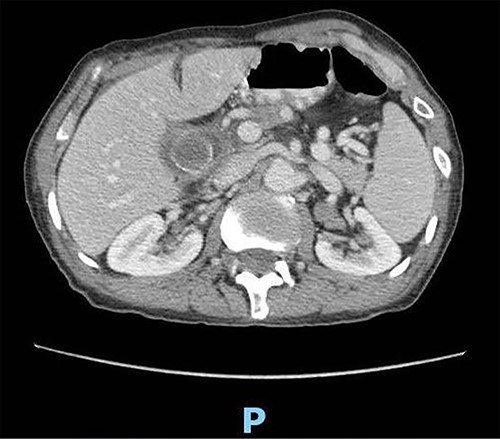

A 89-year-old male patient was admitted to the emergency department complaining of generalized abdominal pain for 4 days. The pain was associated with repeated vomiting and obstipation. He also reported a history of chronic constipation. However, he denied any history of melena, hematochezia, weight loss, night sweats or fever. His past medical history revealed a history of prostatic cancer and pulmonary fibrosis caused by tuberculosis. The patient was diagnosed with symptomatic gallstones two years prior to his presentation, after undergoing an enhanced CT scan of the abdomen (Fig. 1) for abdominal pain. Although he was offered cholecystectomy, he refused the surgery due to his high-risk medical condition.

Enhanced CT scan of the abdomen confirming the presence of a 2.5-cm gallstone.

Upon clinical examination, the patient was vitally stable. Abdominal examination revealed a distended abdomen with generalized tenderness. Digital rectal examination revealed an empty rectum with no palpable masses. Laboratory investigations were unremarkable (Table 1). Abdominal X-ray was done (Fig. 2) and showed dilated large bowel loops suggestive of bowel obstruction. Enhanced CT scan of the abdomen and pelvis was obtained (Figs 3–5) and showed a dilated large bowel loop, with air fluid level. A 2.5-cm gallstone was noted, impacting the sigmoid colon and causing partial large bowel obstruction. There was evidence of pneumobilia with air foci within the gallbladder with a suspected fistula with the hepatic flexure.